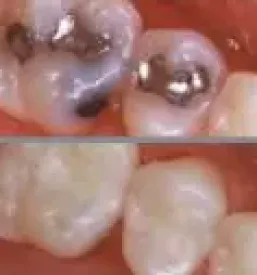

Največkrat ugodno peskanje zob v naši ordinaciji v Ljubljani nudimo strankam, ki imajo površinsko zabarvanje zob zaradi kave, nikotina ali uživanja kakšne druge hrane.

Peskanje zob se opravi tudi z namenom, da odstranimo zobni plak ob protetičnih nadomestkih ali fiksnih zobnih aparatih.